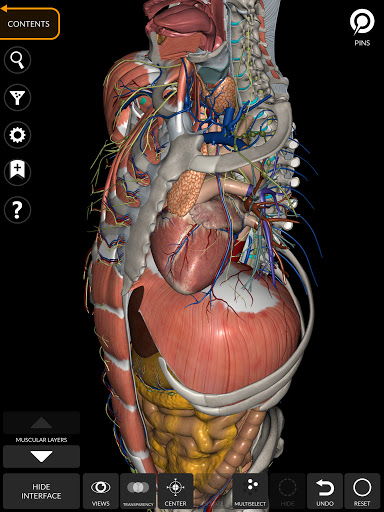

"Anatomy 3D Atlas" дозволяє легко та інтерактивно вивчати анатомію людини.

Завдяки простому та інтуїтивно зрозумілому інтерфейсу можна спостерігати кожну анатомічну структуру під будь-яким кутом.

Анатомічні 3D-моделі особливо деталізовані та мають текстури з роздільною здатністю до 4k.

Поділ за регіонами та попередньо визначені види полегшують спостереження та вивчення окремих частин або груп систем і зв’язків між різними органами.

• Кістково-м’язова система

• Серцево-судинна система

• Нервова система

• Дихальна система

• Травна система